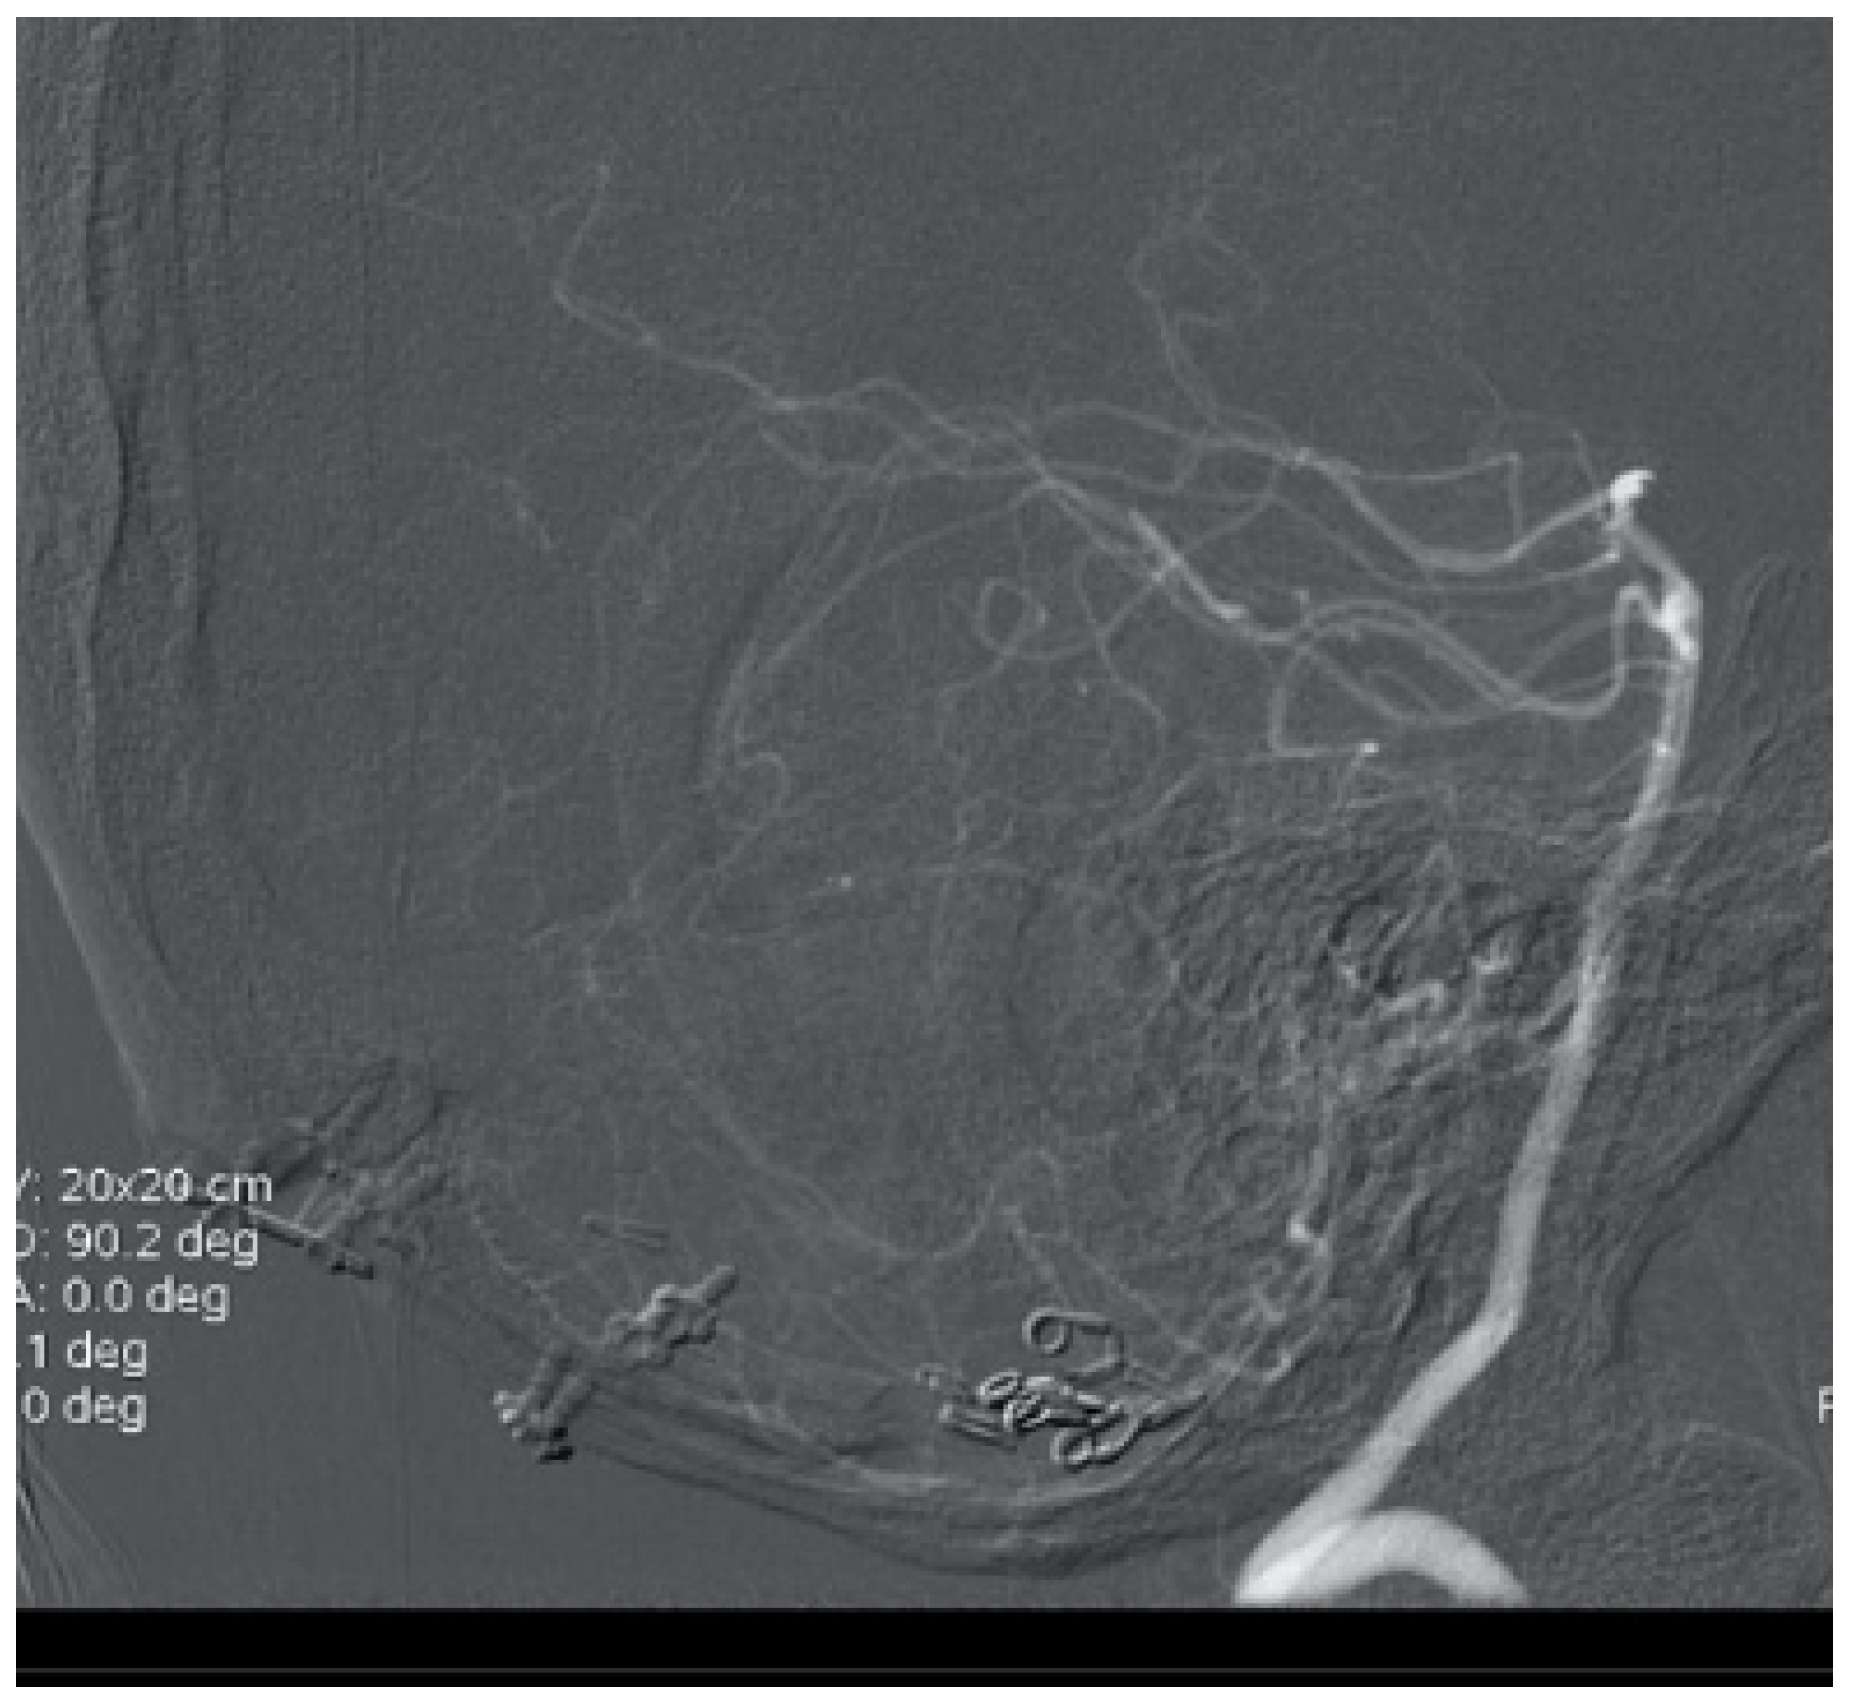

A 72-year-old women woke up with a severe headache. The CT scan showed SAH (Fischer grade IV). The CT angiogram and digital subtraction angiography revealed an aneurysm of the distal PICA (Figure 11) and, according to the age of the patient and comorbidities, endovascular treatment (Table 1) was indicated. The procedure was without complication with complete occlusion of the aneurysm (Figure 12). Because of the massive SAH, she had ventricular drainage for five days. The control CT scan showed a small ischemic lesion of the left cerebellar hemisphere and an obstructive hydrocephalus that was solved by endoscopic third ventriculostomy. After 12 days in the neurosurgical intensive care unit (ICU), she was discharged to a rehabilitation center with improving neurological status.

Figure 12. Complete coil embolization of the PICA aneurysm.